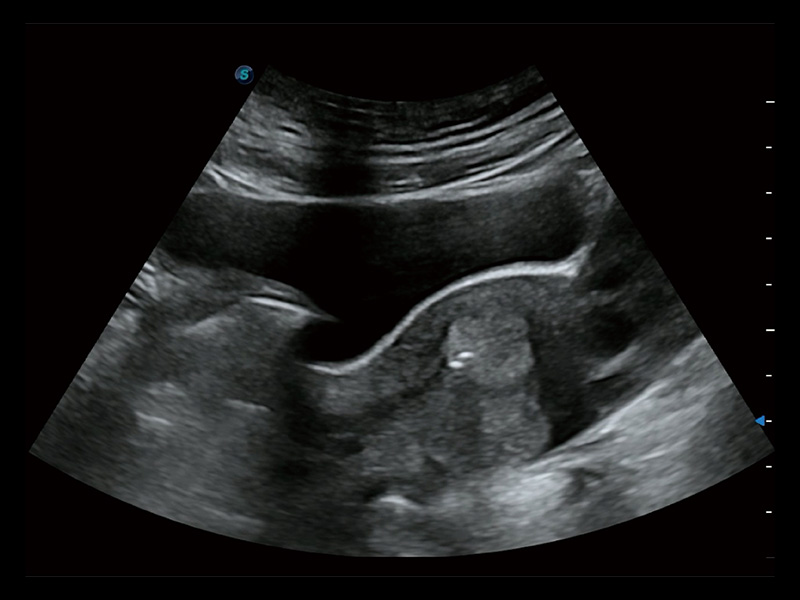

窥器式探头

采用弯柄探头替代窥器下叶,巧妙实现了实时超声监控下的单人手术操作。探头频率高、图像清晰,不受肥胖影响,使得手术过程中无需充盈膀胱,即可有效进行胚胎移植、减胎手术的精准操作。

超声引导下胚胎移植